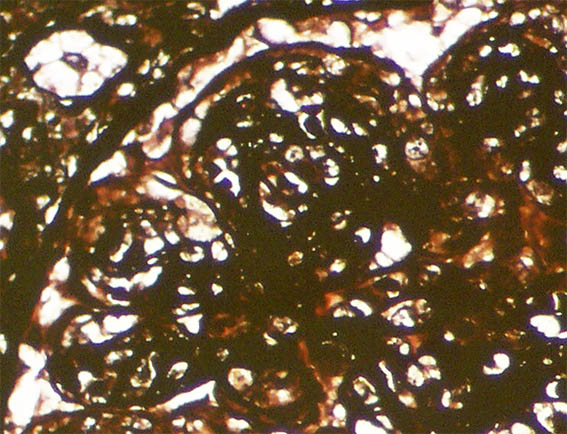

Figure 9. Methenamine-silver stain, X1,000.